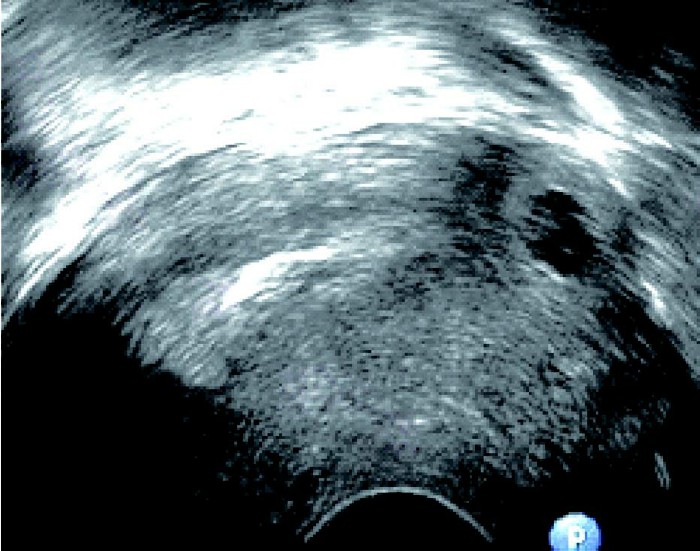

患者,女,25 岁。停经56 天,尿HCG(+),外院人工流产失败转来本院。经阴道超声检查显示:子宫横切面,宫腔内未见胚囊,右宫角突起肌层内见胚囊、胚芽、胎心,胚囊与宫腔不相通。

超声诊断:右宫角肌层内见胚囊、胚芽、胎心,间质部妊娠。

手术病理:(右)输卵管间质部妊娠。